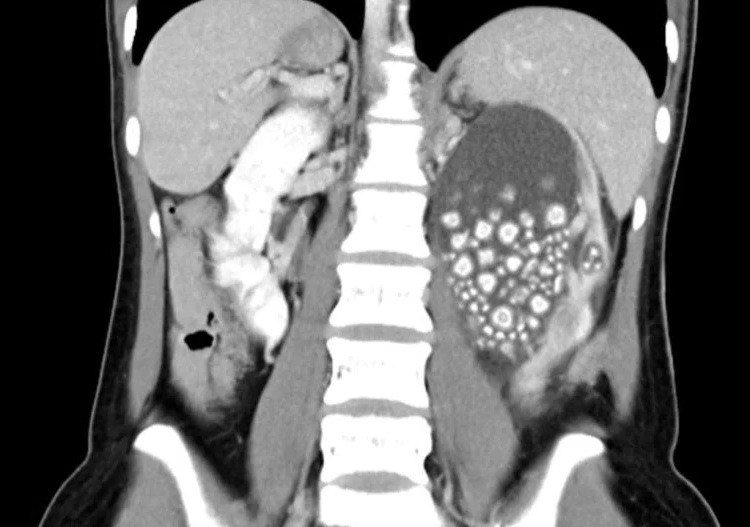

Молодая женщина, которую тайваньские СМИ опознали как Сяо Юй, в начале этого месяца была госпитализирована в больницу города Тайнань после того, как пожаловалась на сильную боль в пояснице. У нее также была лихорадка, а анализ крови показал необычно высокое количество лейкоцитов. Врачи назначили компьютерную томографию, которая показала, что правая почка Юя полна жидкости и практически полна камней. Первым делом было назначить молодой женщине антибиотики, затем слить жидкость из ее почки и, наконец, провести минимально инвазивную операцию по удалению сотен камней.

В итоге врачи извлекли более 300 камней размером от 5 мм до 2 см. По данным Taiwan News, большинство камней по внешнему виду напоминали «маленькие приготовленные на пару булочки».